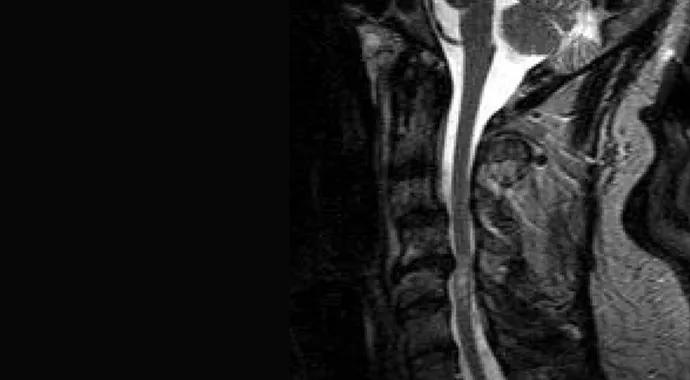

The clinical presentation and symptom progression of multiple sclerosis (MS) can overlap with those of other pathologies, making the underlying condition difficult to diagnose and treat. Specifically, cervical stenosis with myelopathy (CSM) can present with MS-like symptoms including gait ataxia, extremity weakness, spasticity and sensory loss due to spinal cord compression. When the two diseases occur concurrently (Figure), management is exceedingly difficult. While MS therapy involves immunomodulatory medications, CSM is often treated with surgical decompression. Furthermore, it is difficult to discern which disease process is responsible for the symptoms.

Figure. Sagittal T2-weighted MRI of a patient with MS and cervical stenosis with myelopathy.